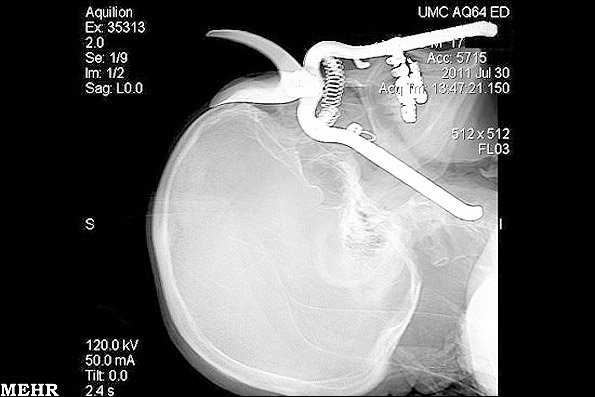

کشف یک قیچی باغبانی در جمجمه

تصویر سیتی اسکن که از سوی مرکز پزشکی دانشگاه توکسان منتشر شده است، یک قیچی باغبانی را در سر یک مرد 86 ساله ساکن "گرین ولی" در آریزونا را نشان می دهد. این عکس قبل از عمل جراحی این مرد در 30 جولای 2011 گرفته شده است.

"لروی لوتشر" درحالی که مشغول کار در حیاط خانه خود بود یک قیچی باغبانی به روی سرش افتاد. وی برای جلوگیری از برخورد قیچی به چشمهایش از دستان خود استفاده کرد اما قیچی وارد گردنش شد.